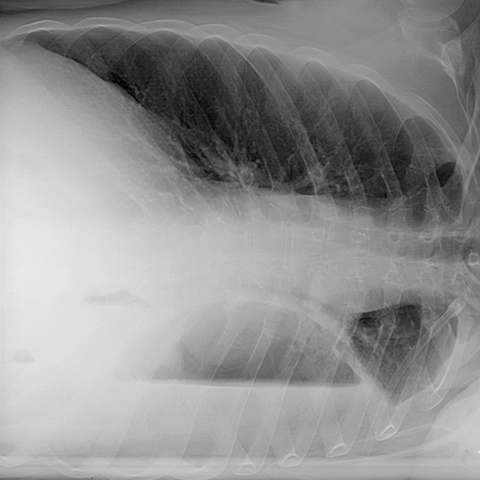

Left Empyema (Left Lateral Decubitus CXR) [2 of 2]